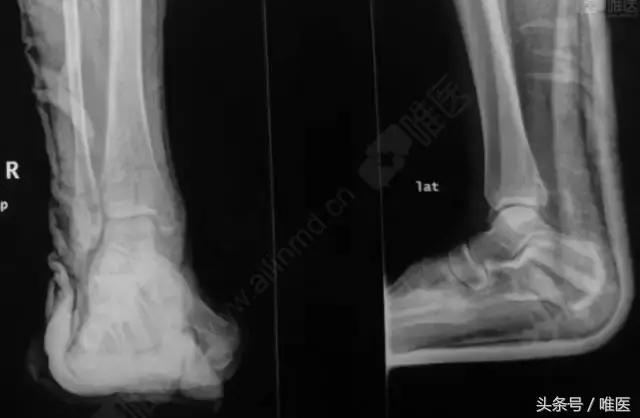

X线:右侧踝关节骨折

L-H分型:旋后外旋型 IV度;

Danis-Webber分型:B型